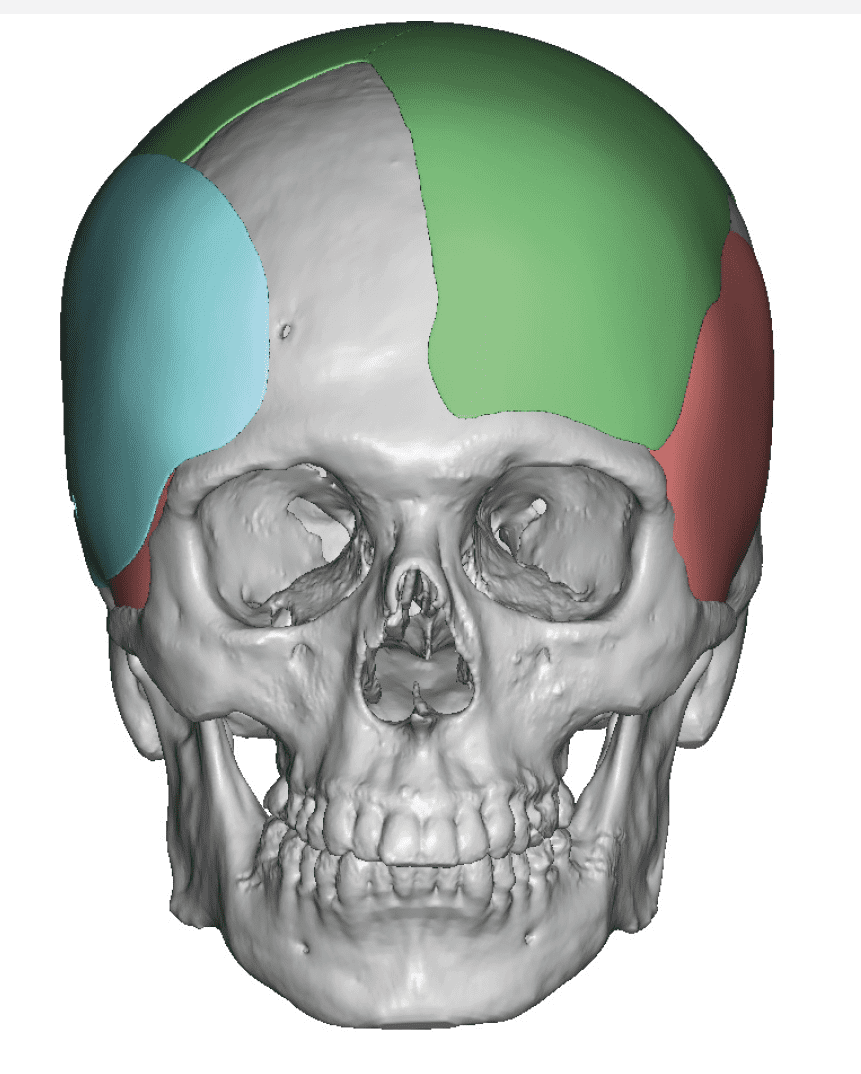

Desire for change of head shape from front view form an inverted V shape to a rounder and wider head shape.

Placement of custom extended forehead-temporal implants through incisions in the crease behind the ear. (he had a prior back of head skull implant which is green in the implant designs and which the head widening implants partially covered it)

Desire for change of head shape from front view form an inverted V shape to a rounder and wider head shape.

Placement of custom extended forehead-temporal implants through incisions in the crease behind the ear. (he had a prior back of head skull implant which is green in the implant designs and which the head widening implants partially covered it)